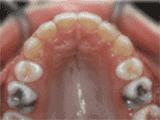

第四种:

牙列拥挤,牙槽骨过窄,牙齿没有足够空间,只好前后左右高低上下乱长,经过矫正后的牙齿是这样的~